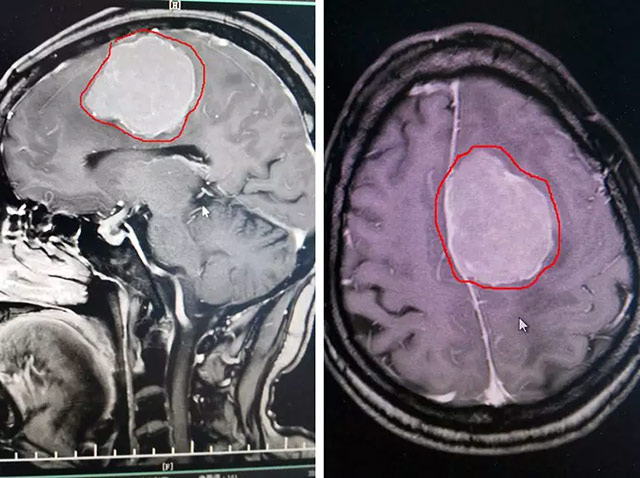

經(jīng)檢查,患者有明顯右側(cè)肢體乏力、精細運動差,并有思維遲緩、語言遲緩、記憶力下降等癥狀。頭顱MR增強顯示,患者左側(cè)大腦鐮旁有巨大團塊狀異常信號,腫瘤大小約5公分,如雞蛋大小。該腫瘤巨大,壓迫癥狀明顯,周圍水腫。且有繼續(xù)增大的趨向,導致顱內(nèi)壓進一步升高,形成腦疝,有危及生命的可能。

▲ 患者顱內(nèi)腦膜瘤如雞蛋大小,可能危及生命